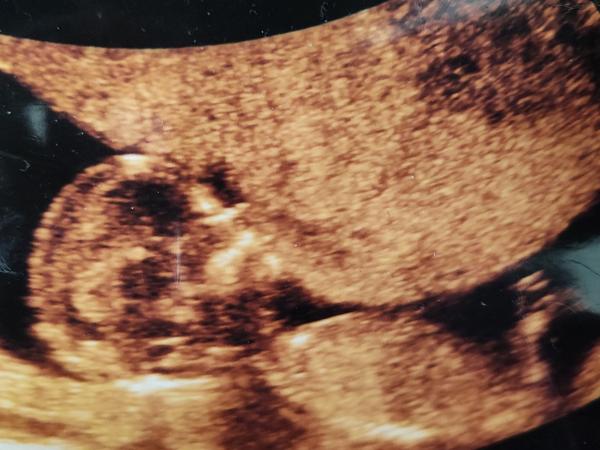

Holky včera jsem(16tt) byla na dalších odberech krve screening mám psany jako negativní ale prý mám velmi nízkou hodnotu free-B hcg🤔(27,33 IU/I 0,36 korigovany mom) sestricka říkala ze je možné,že jsem dost hubena v 16tt 48kg a že je důležitý ze screening je negativní a porovnaji to hcg teď s odběry z 16tt podle ultrazvuku ze včera to vypadá na holcicku měla jste některá taky tak nízké hcg a vse bylo ok?😖